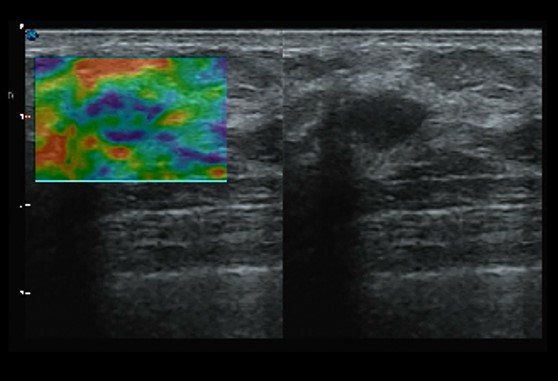

Hình ảnh C-Xlasto

Với C-xlasto Imaging, P20 cho phép phân tích độ đàn hồi định lượng toàn diện. Trong khi đó, C-xlasto trên P20 được hỗ trợ bởi các đầu dò tuyến tính, lồi và xuyên âm đạo, để đảm bảo khả năng tái lập tốt và kết quả đàn hồi định lượng nhất quán cao.